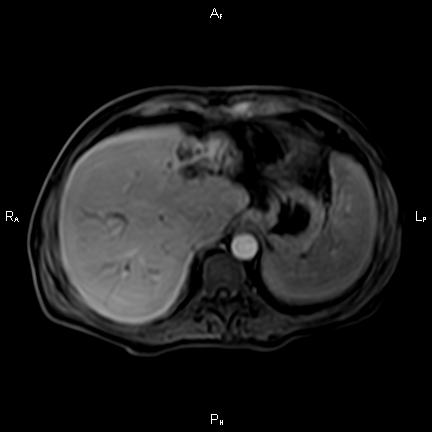

Ανώδυνος ίκτερος και παθολογικά ηπατικά ένζυμα. Ιστορικό πιθανής σκληρυντικής χολαγγειίτιδας

Μαγνητική τομογραφία.

Οι αρχικές εξετάσεις εκλογής, όσον αφορά τον απεικονιστικό κυρίως έλεγχο, σε ασθενή προσερχόμενο στο Νοσοκομείο με αποφρακτικό ίκτερο, είναι το υπερηχογράφημα και η αξονική τομογραφία. Οι εξετάσεις αυτές έχουν αποδειχθεί ικανές να προσδώσουν έμμεσα και άμεσα στοιχεία για τη διάγνωση του χολαγγειοκαρκινώματος, όμως κυρίαρχη εξέταση για την διάγνωση του χολαγγειοκαρκινώματος είναι η μαγνητική τομογραφία (MRI, MRCP, MRA).